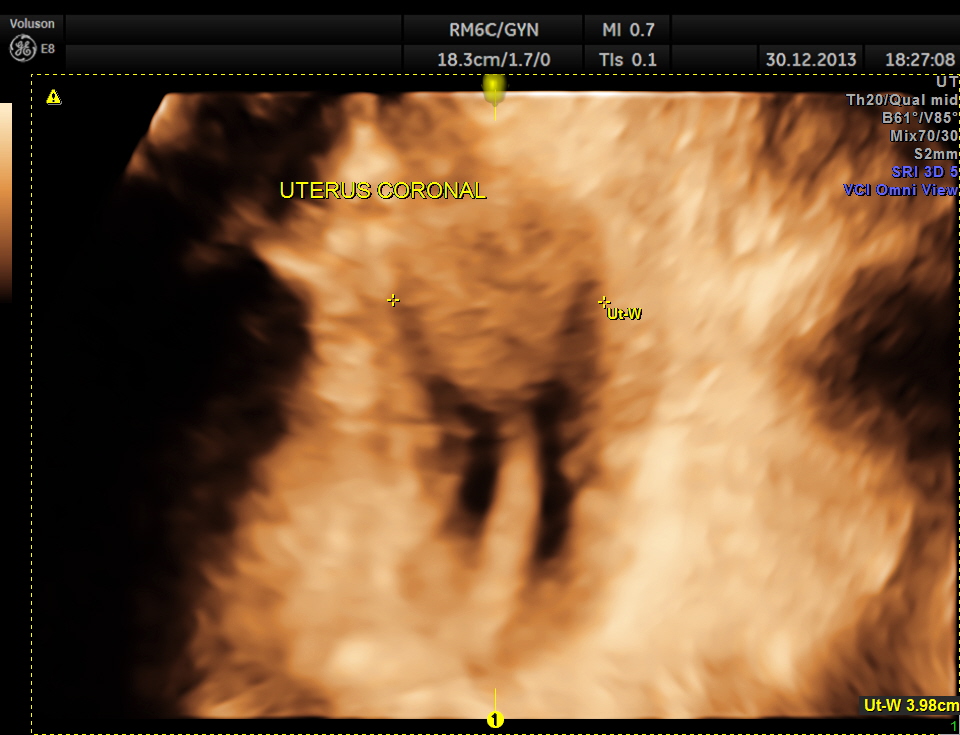

the next is a coronal view of the uterus.